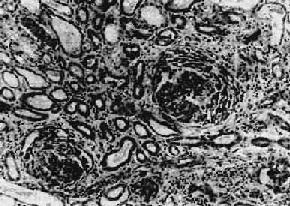

图12-22弥漫性硬化性肾小球肾炎

肾小球纤维化,玻璃样变;肾小管也大部分萎缩纤维化;间质纤维组织增生,有多数慢性炎细胞浸润

图12-23弥漫性硬化性肾小球肾炎

大量肾小球纤维化,玻璃样变,相互靠近、集中,残存的肾小球呈代偿性肥大